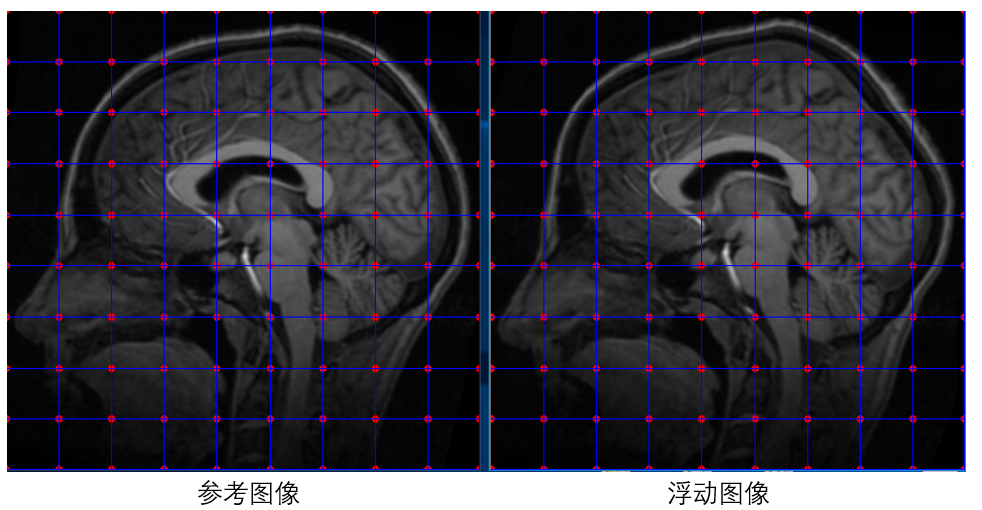

基于此方法,我们不必去找特征点并计算特征点的匹配,在配准开始之前,我们只需要在参考图像与浮动图像上面初始化一系列等间距的点,并假设两图中相同位置的点为匹配点对,然后在此基础上使用梯度下降法一步一步优化浮动图像上初始点的位置,使得浮动图像与参考图像上的点达到真正的匹配。如下图所示:

在这里需要强调的是,我们并不需要优化参考图像上点的位置,我们只需要固定参考图像上点的位置,然后优化浮动图像上点的位置,使其与参考图像上点的位置匹配即可。所以,上面我们说目标函数的输入参数是参考图像与浮动图像的匹配点对,其实需要优化的只有浮动图像上点的位置。假设参考图像与浮动图像上初始化的等间距的点个数都是N个,每个点包含x坐标和y坐标,那么我们需要优化的参数为浮动图像上所有初始化点的x、y坐标组成的2*N个参数。

(8) 测试代码

使用以上实现的配准方法,对脑部图像进行配准。

init_points(img1, row_block_num, col_block_num, p1, p2); //在参考图像与浮动图像上分别初始化等间距点